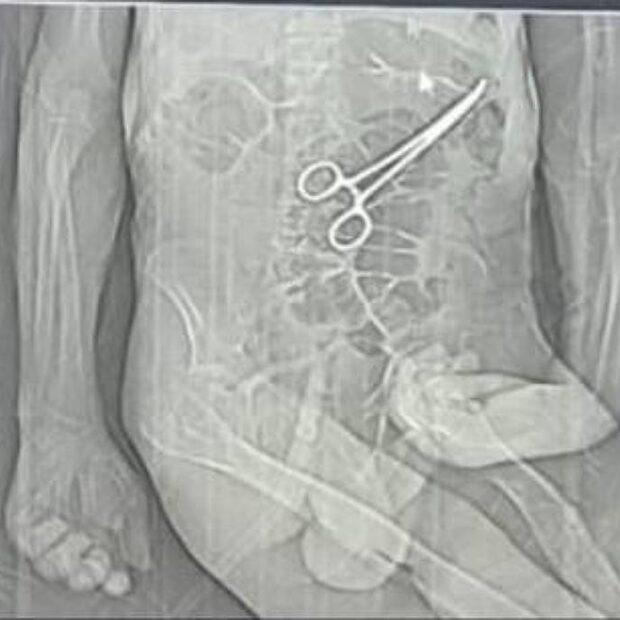

Família acusa hospital de esquecer pinça em corpo de idoso morto na véspera do Natal em MG

A família de um aposentado que morreu na véspera do último Natal em João Pinheiro, no noroeste de Minas Gerais, acusa médicos do hospital municipal de esquecerem uma pinça no abdômen do idoso durante uma cirurgia feita semanas antes do óbito.

Após a cirurgia, o paciente voltou a apresentar sintomas graves, o que levou à realização de novos exames. Nesse momento, uma tomografia identificou, segundo a secretaria, “um corpo estranho na cavidade abdominal”.

Os parentes também afirmam que só souberam do que de fato havia ocorrido por meio de uma reportagem de uma rádio local, quando tomaram conhecimento da imagem de uma tomografia indicando uma pinça no abdômen de Manoel.